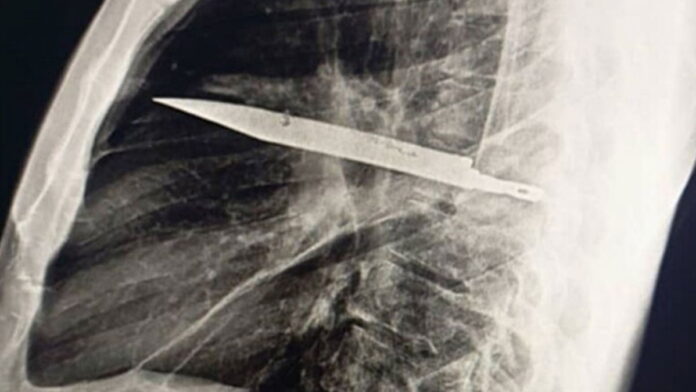

Żył osiem lat z nożem w klatce piersiowej

Mężczyzna żył przez 8 lat z nożem w klatce piersiowej.